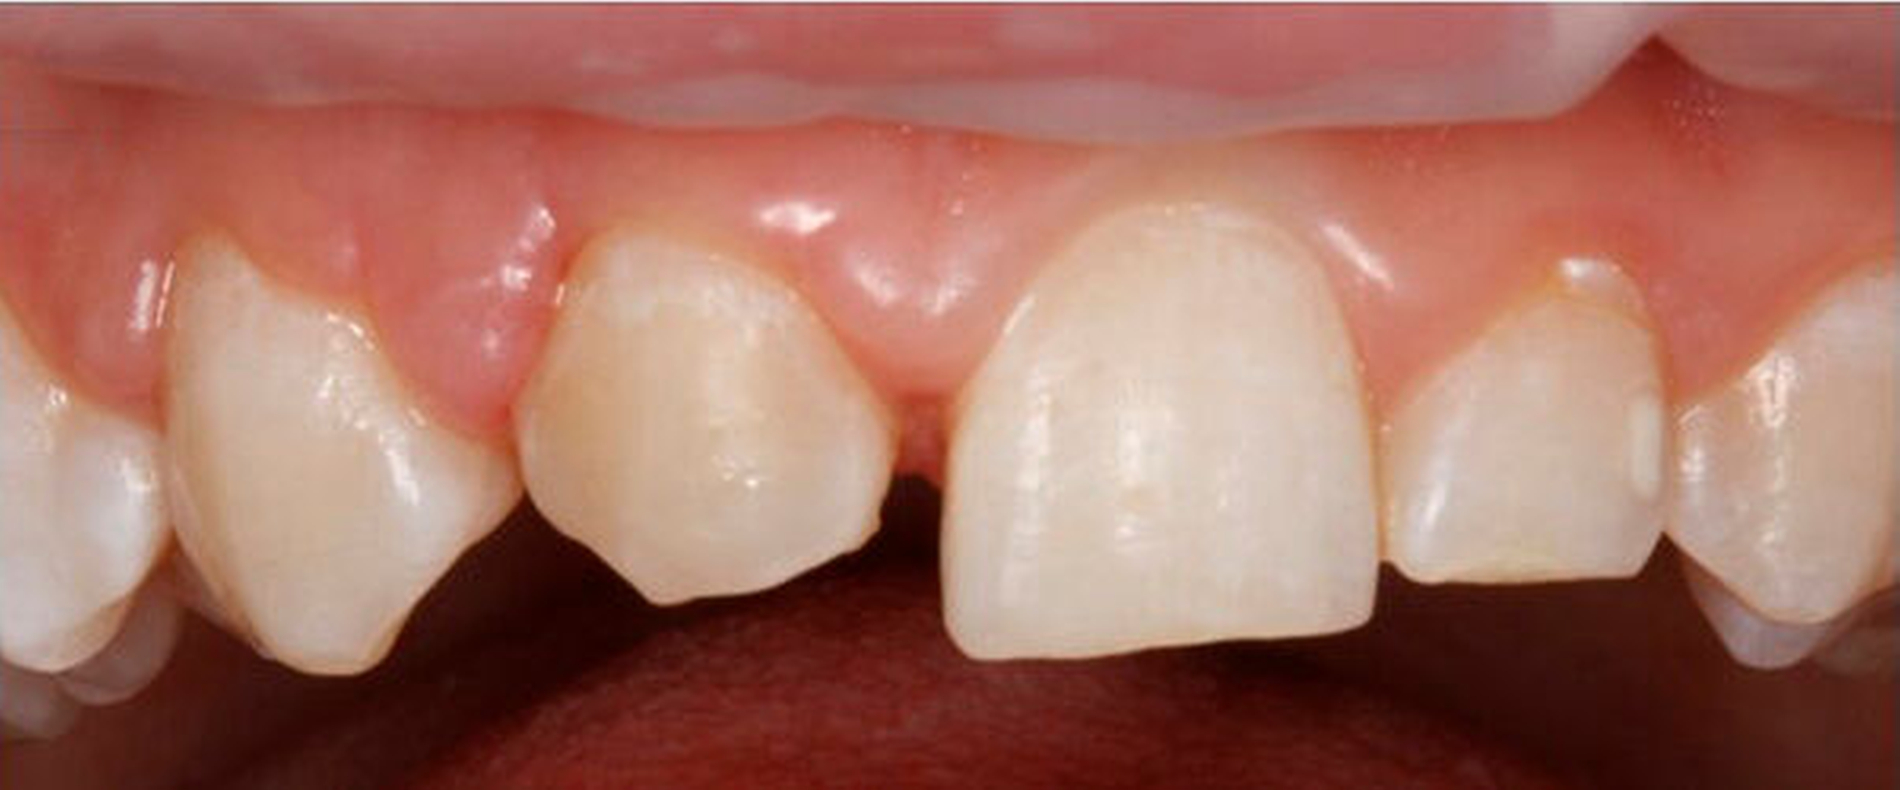

Die Rekonstruktion von Zähnen mit Komposit ermöglicht eine direkte und maximal zahnerhaltende Therapie, bei der die Zahnhartsubstanz nicht oder nur minimal im Sinne einer Anschrägung abgetragen werden muss. Im Vergleich zur Rekonstruktion mit keramischen Veneers muss dabei in der Regel wesentlich mehr Zahnhartsubstanz geopfert werden, um die nötigen Keramikschichtstärken einhalten zu können. Reparaturen, Farb- und Formanpassungen lassen sich mit der Komposittechnik im Vergleich zu Keramikrestaurationen immer wieder anpassen. Insbesondere bei jungen Patienten im Wachstum ist dies von Vorteil, um bei Veränderungen der Gingivaverhältnisse die rekonstruierten Zähne ihren Nachbarzähnen anzupassen (Verschluss schwarzer Dreiecke, zervikale Ausformungen).